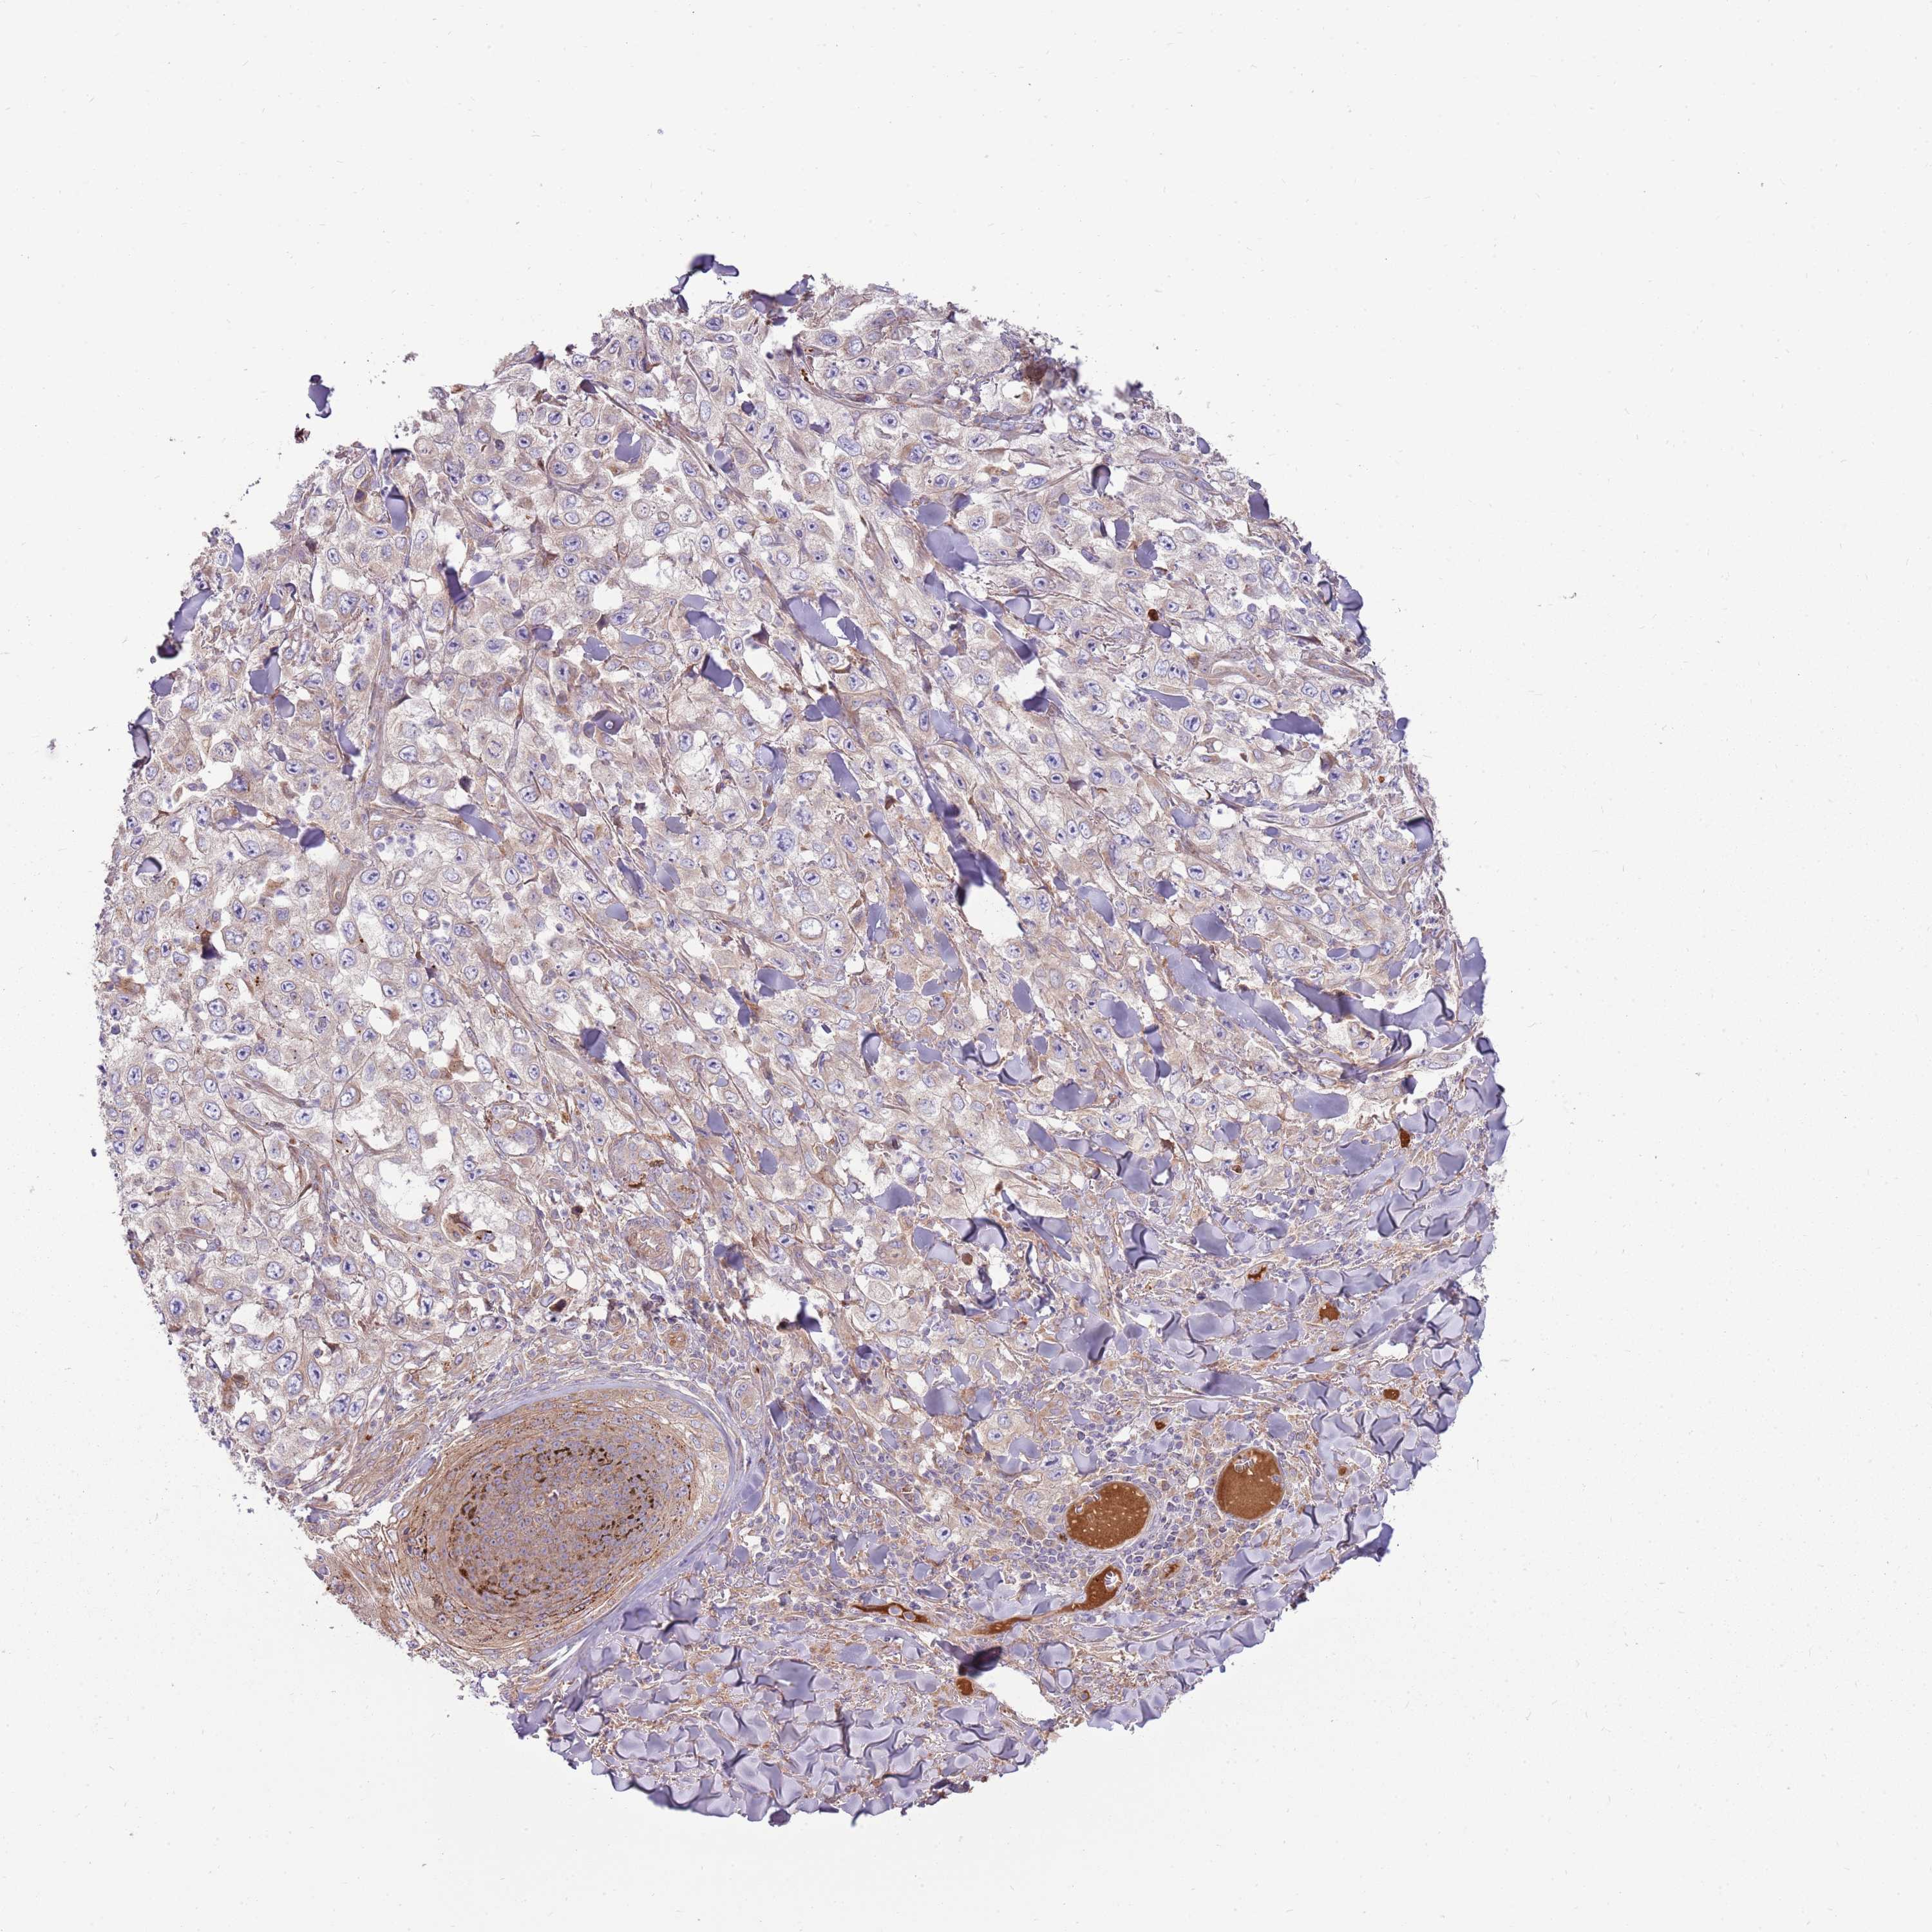

Basal cell and squamous cell cancer

SKIN CANCER - Protein expressioni

A mouse-over function shows sample information and annotation data. Click on an image to view it in a full screen mode. Samples can be filtered based on level of antibody staining by selecting one or several of the following categories: high, medium, low and not detected. The assay and annotation is described here.

Each image is clickable and will lead to virtual microscopy that enables deeper exploration of all samples and also displays staining intensity scores, fraction scores and subcellular localization as well as patient and tissue information for each sample.

Antibody HPA048904

Staining

High

Medium

Low

Not detected

Intensity

Strong

Moderate

Weak

Negative

Quantity

>75%

75%-25%

<25%

None

Location

Nuclear

Cytoplasmic/membranous

Cytoplasmic/membranous,nuclear

Squamous cell carcinoma, NOS

Squamous cell carcinoma, metastatic, NOS